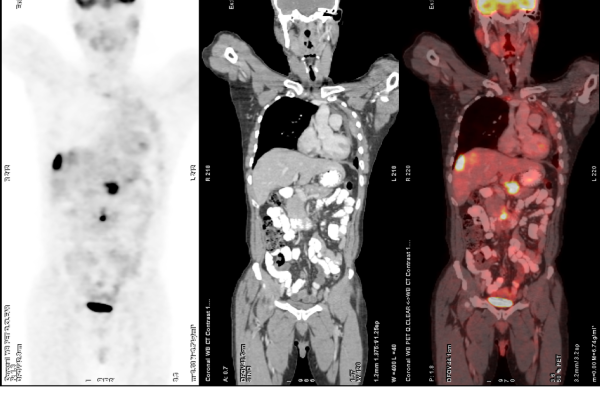

FDG-PET-CT

FDF PET-CT

FDG PET-CT is one of the most advanced and widely used imaging techniques in modern medicine, especially for cancer evaluation. It works by detecting areas of increased glucose metabolism in the body, which is a common characteristic of active cancer cells, infections, and certain inflammatory conditions. By combining the metabolic insights from PET with the anatomical detail of CT, FDG PET-CT offers exceptional accuracy in locating and characterizing disease. This scan plays a critical role in the diagnosis, staging, and treatment planning of a wide range of cancers. It also helps assess how well a tumor is responding to therapy and can detect recurrence at an early stage, often before it becomes visible on conventional scans.

Key Applications:

• Initial staging of various cancers (lung, breast, lymphoma, etc.)

• Monitoring treatment response

• Detecting tumor recurrence or metastasis

• Whole-body oncological assessment